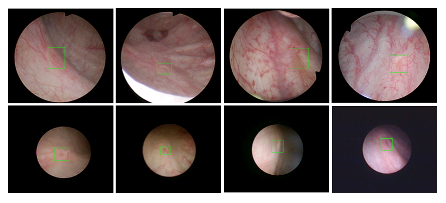

福利姬 医疗机器人研究院—深睿医疗人工智能医学视频联合实验室成立于2018年7月。PI包括来自于交大生医工学院和电院的三位教授,平台建设目标是将人工智能实时地用到临床医学中去,研究方向包括:1. 建立内窥镜人工智能辅助诊断系统,通过对病灶和解剖结构的实时识别来辅助医生更好地进行微创诊断和治疗;2. 以个性化、定量化的精准诊疗技术为研发目标,重点开展医学影像智能诊断、医学可视化及计算机辅助手术规划、AI及大数据分析在临床诊疗流程中的集成应用等方向的研发。试图利用AI技术、大数据分析技术、3D打印技术、虚拟现实及增强现实技术促进临床的影像诊断、治疗方案设计、预后预测分析等诊疗环节的智能化提升与技术变革;3. 面向运动医学康复、神经退行性疾病量化诊断,以及其他与人体运动相关的疾病诊疗、康复应用,开展视觉三维人体运动的测量、分析与识别研究,通过基于深度学习的视觉检测识别以及相关大数据分析,为相关疾病的诊疗和康复提供AI辅助。具体临床应用包括:关节镜手术术后康复指导和评估、帕金森病的量化诊断、精神疾病的量化诊断与评估、儿童异常行为分析等。

近年来,联合实验室发展了泌尿镜手术实时识别技术,人体姿态精确识别技术,另外围绕小儿先心病手术、肝癌消融手术、数字口腔诊疗的智能化提升等内容进行应用研发。